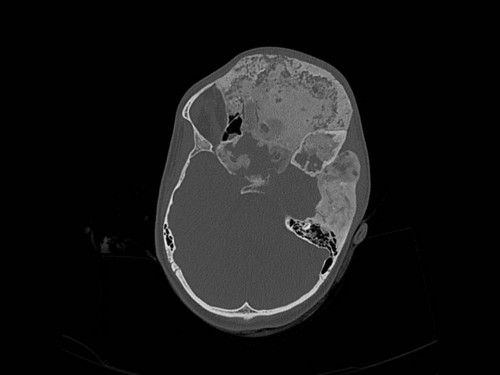

Knochendeformitäten seit der Geburt

Fall-ID: 712

ICD: M85.09

Autor*in: Sandra Klipp

Eine 16-jährige Patientin kommt in eine MKG-chirurgische Praxis zur Abklärung der weiteren Vorgehensweise bzgl. ihrer Erkrankung.

Sie betrachten die angefertigten Röntgenbilder. Welche der folgenden Röntgenbefunde ist korrekt? Ossäre Auftreibungen im Bereich …

- A… der Mandibula links.

- B… des Os frontale links.

- C… des Os zygomaticum links.

- D… des Os temporale links.

- EAlle genannten Aussagen sind korrekt.

Bildgebung - OPAN 2004